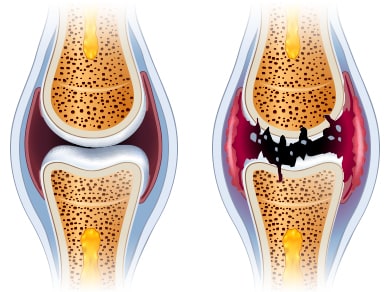

관절에 염증이 생기면 주변의 혈관이 확장되어 더 많은 혈액이 관절에 도달하게 됩니다

근육의 위축과 관절의 구축은 관절의 기형을 유발하게 되며, 관절의 연골이 닳아서 관절에 소리가 날 수 있습니다. 또한 관절의 열이 나거나 발적이 나타날 수 있고 관절이 변형되어 굽은 다리로 진행될 수 있습니다.

관절은 초기에 빨리 발견하기가 어렵다고 하는데 그 이유는 연골은 신경세포가 없기 때문에 손상을 입어도 자각하기가 쉽지 않기 때문입니다.